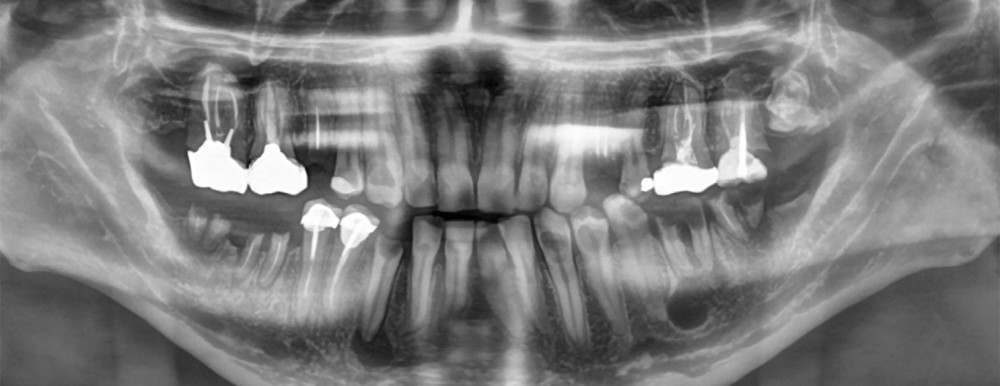

Le kyste radiculo-dentaire (fig. 1 et 2), également retrouvé sous le terme de kyste apico-dentaire, ou radiculaire, est le plus fréquent des kystes des maxillaires [1]. Il s’intègre dans la grande famille des tumeurs bénignes osseuses odontogéniques et maxillo-faciales (classification internationale de l’OMS, 2017). Il se développe aux dépens d’un granulome péri-apical secondaire à une nécrose dentaire. Le mécanisme physiopathologique à l’origine de la formation kystique est la prolifération de débris épithéliaux (débris de Malassez) présents dans le desmodonte sous l’action de stimuli inflammatoires. Un kyste est constitué d’une membrane épithéliale et d’une cavité plus ou moins liquidienne, voire solide dans certains cas. On y retrouve des cristaux de cholestérol, des calcifications dystrophiques d’exsudat inflammatoire, des macrophages, des plasmocytes, des cellules ciliées, muqueuses, géantes multinuclées et, dans certains cas, des globules rouges.

On distingue classiquement le granulome (- 1 cm) du kyste (+ 1 cm). Ce dernier possède des parois propres et des contours réguliers bien délimités. Le développement kystique s’accompagne volontiers d’un refoulement des structures avoisinantes, les corticales osseuses apparaissent soufflées, dans certains cas, amincies, pouvant venir empiéter sur des éléments anatomiques de la sphère maxillo-mandibulaire (sinus, canal mandibulaire, fosses nasales, foramen mentonnier…) (fig. 3).